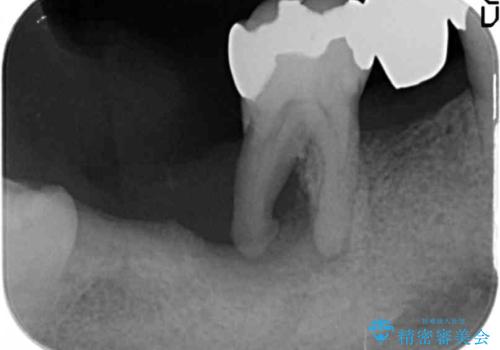

- 歯周病で失った奥歯や、グラグラしている歯の治療を希望され来院されました。

残すことのできない歯を抜去したのち、骨を造成し安定した環境下で長期的な予後を期待できるインプラント治療を計画します。